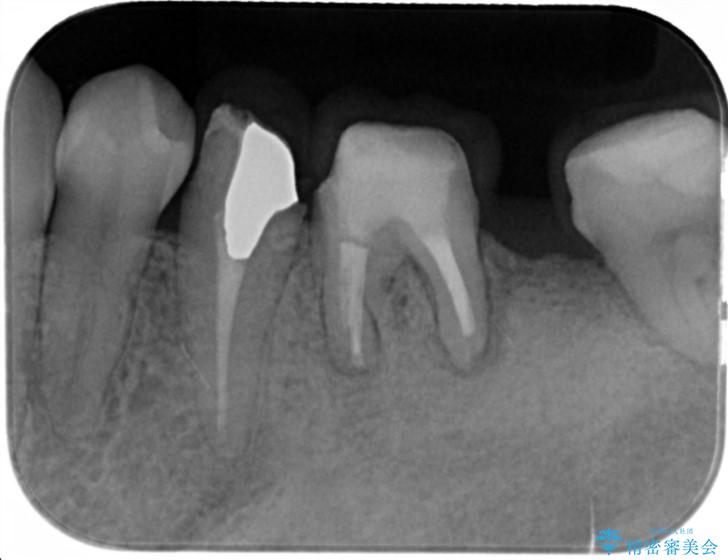

- 他院で根の治療まで終え、違和感が取れず相談に来院されました。

当該歯を精査したところ、歯根に破折が見られ抜歯を余儀なくされました。

抜歯後、インプラントを用いて咬合機能を回復すると共に周囲に強固な角化歯肉を移植することによりより長期にわたり安定したインプラント周囲環境となるよう治療を計画します。